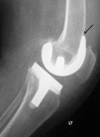

Today, total knee arthroplasty (TKA) is one the most commonly performed surgeries worldwide. The purpose of this article is to review the appearance of normal post-TKA roentgenographs and describe the correct sequence for their interpretation. It is unwise to depend solely on patients' symptoms when diagnosing TKA complications because serial radiographs can foresee failures well before they manifest clinically. Ideal post-TKA radiographs comprise whole lower extremity anteroposterior and lateral views taken under weight bearing conditions along with a skyline view of the patellofemoral joint. Among other things, weight bearing exposes the true alignment, ligamentous laxity and polyethylene wear. On the basis of follow-up of our TKA cases, we have drawn up a protocol for assessing postoperative X-ray films after TKAs. Following the proposed sequence, surgeon can easily decide how to proceed with follow-up and foresee complications. Careful interpretation of postoperative radiographs after TKA is essential to careful monitoring of patients and implant survival.